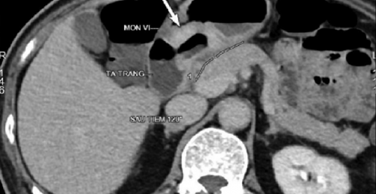

+ Chụp cắt lớp vi tính ổ bụng trước mổ: Dày thành không đều vùng hang môn vị, nơi dày nhất 15mm, không thấy thâm nhiễm xung quanh. Tổn thương sùi lỗ môn vị chiếm hết ½ chu vi môn vị mạc treo lân cận có 4 hạch, kích thước lớn

Hình 3. Hình ảnh chụp cắt lớp vi tính ổ bụng trước phẫu thuật: Tổn thương sùi lỗ môn vị chiếm hết ½ chu vi môn vị (mũi tên trắng)